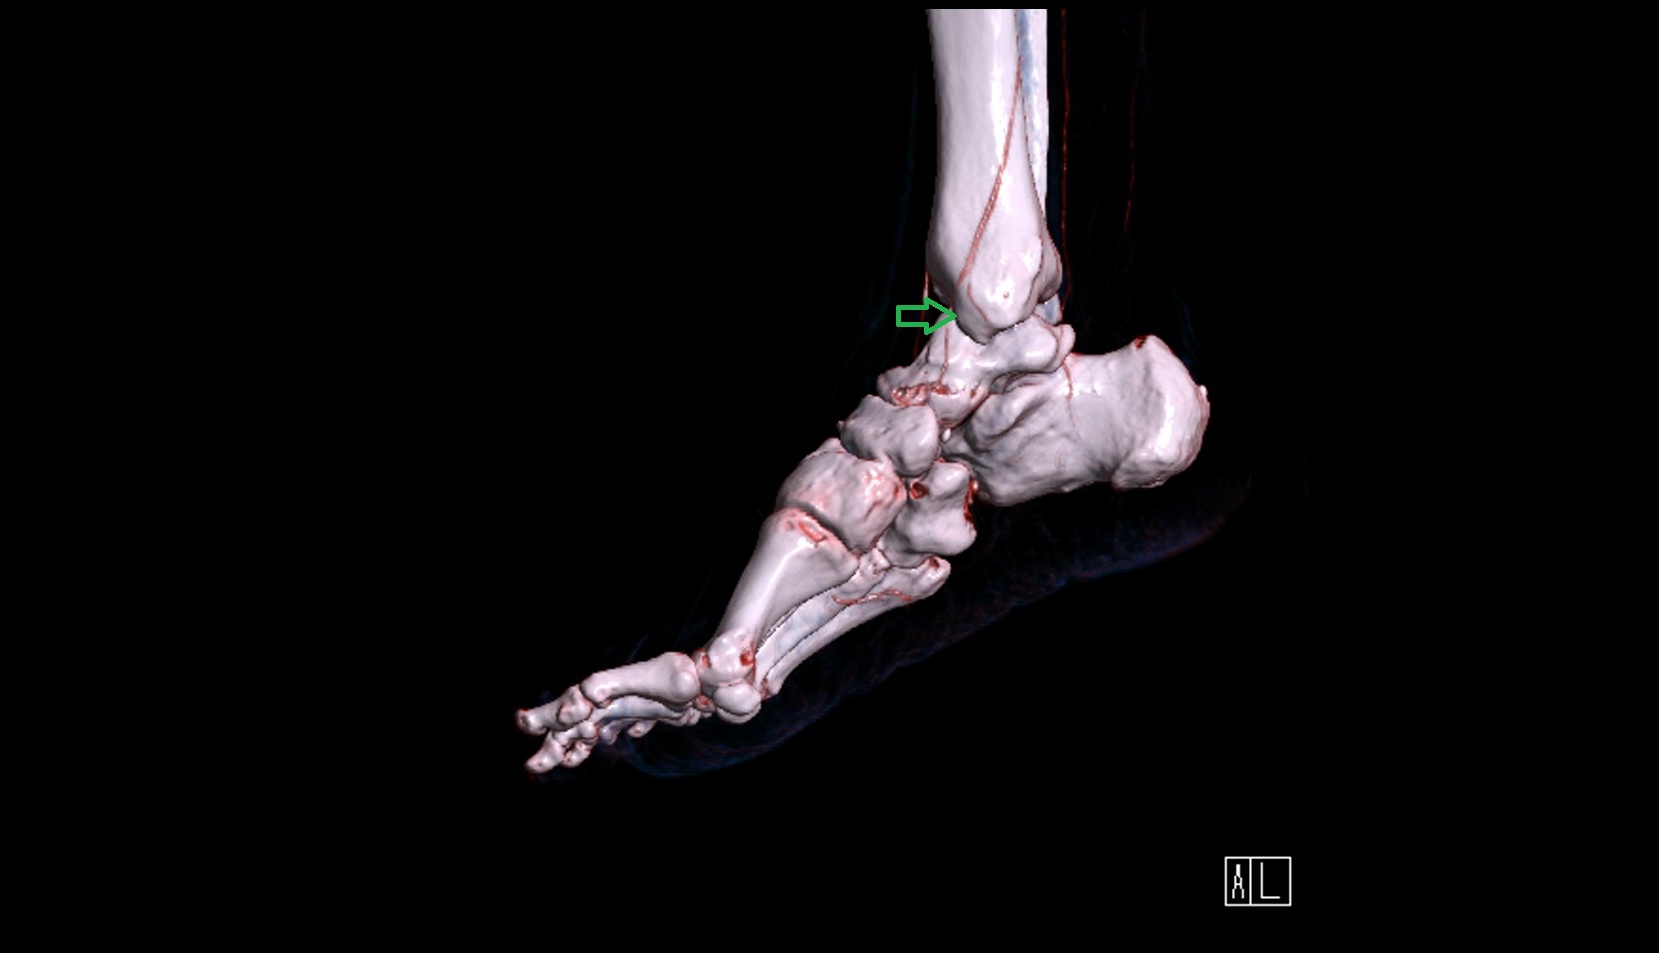

- Talus

- Head of talus

- Body of talus

- Neck of talus

- Calcaneus

- Medial malleolus

- Lateral malleolus

- Ankle joint

- Talocalcaneal joint